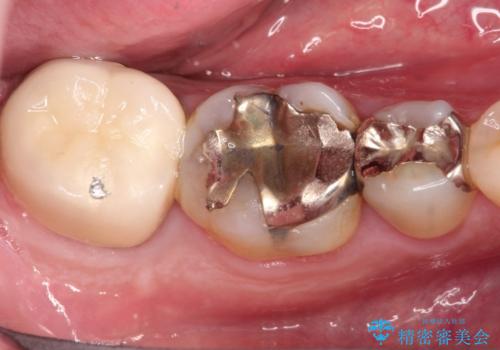

- 「硬い物を食べたら歯が割れた」を主訴に来院された患者さんです。

根っこのところまで歯が割れていたため、歯を残すことは不可能と診断し抜歯後、インプラントで治療を行いました。

破折の深さが歯根まで及んでいたため抜歯を行いました。